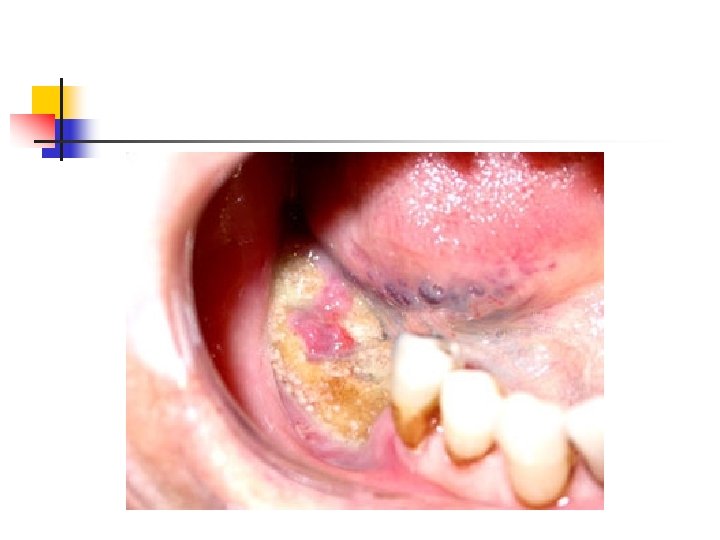

Bisfosfanatlar n n Osteoklastik kemik rezorbsiyonunu inhibe ederler Mandibula osteonekrozu n n Özellikle zoledronik asid kullanılanlarda Tolidomid + bisfosfonat kullanımında artmış risk

n n 6 aydan uzun süren bifosfanat kullanımı Diş çekimi Periodontal ameliyatlar İmplant operasyonları

Lösemi-Lenfoma-Myelomda Diş Hekimliği

n İmmün sistem baskılanması nedeniyle enfeksiyon riskinde artış Doku iyileşmesinde gecikme n KT alan hastalarda enfeksiyon ve kanama riski n n n Lökosit / Nötrofil sayısı, Trombosit sayısı, kanama zamanı Özellikle Baş-boyun bölgesine yapılan RT sonrası kserostomi, osteonekroz gibi sorunlar

Dikkat n n n Dişeti hipertrofisi Kanama diyatezi Gerekirse hemogram bakısı Konsültasyon istemi Remisyonda olan hastanın dental girişimlerini hızla tamamlama